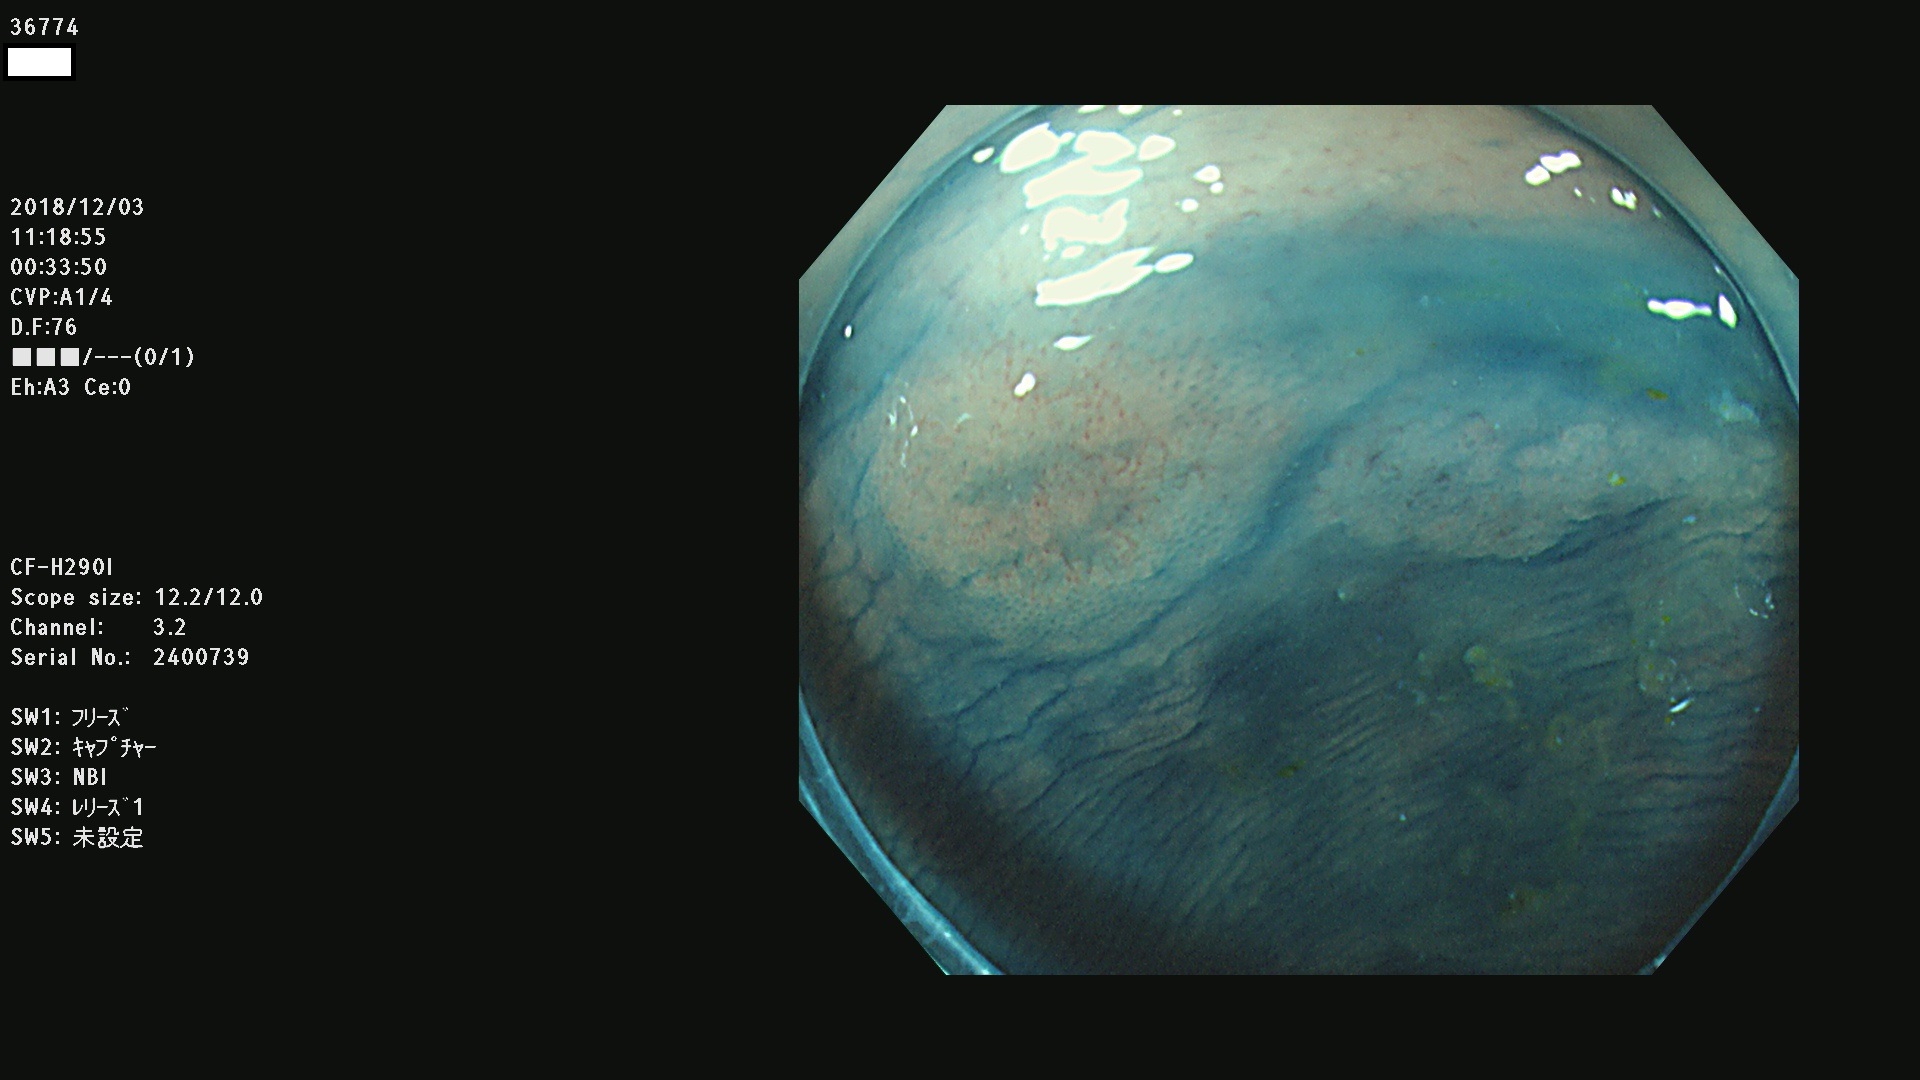

36700 36701 36702 36704 36705 36707 36708 36710 36712(SSAPのみ) 36714 36715 36716 36717 36718 36721 36723 36724 36730 36731 36732 36734 36735 36736 36738 36739 36742 36744 36745 36746 36749 36752(SSAPのみ) 36754 36756 36758 36759 36760 36731 36732 36734 36737 36738 36739 36771(SSAPのみ) 36772 36773 36774 36775 36776 36777 36780 36781 36783 36785 36786 36788 36790 36792 36794 36797 36798